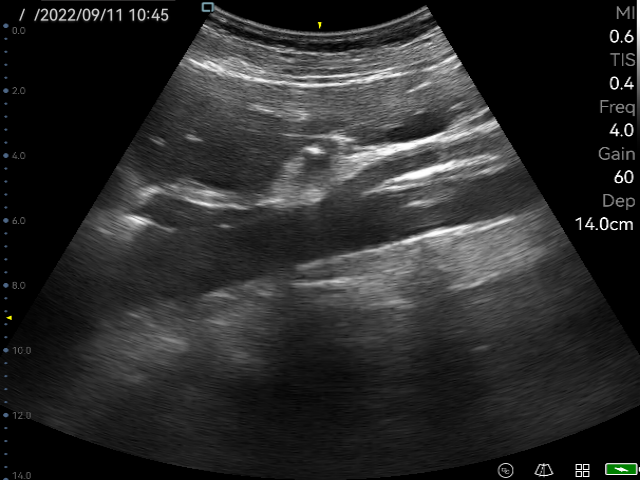

Image Quality and Resolution

The P50 adopts an advanced front-end image processing and post-processing platform. As a result, the P50 provides incredible detail resolution and contrast resolution, nearly equal to traditional-mid range ultrasound systems. With amazing image quality, doctors are able to make more accurate clinical decisions.